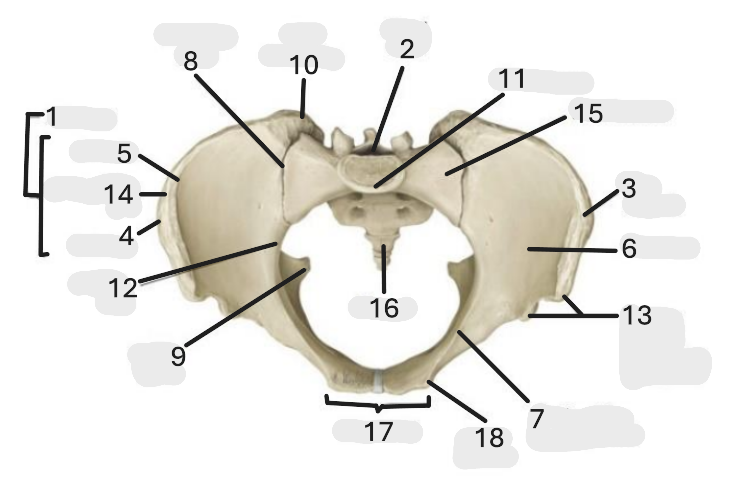

Where is the iliac crest

1

where is the sacral canal

2

Where is the iliac tubercle

3

Where is the outer lip

4

Where is the inner lip

5

Where is the iliac fossa

6

Where is the pectineal line (pecten pubis)

7

Where is the sacroiliac joint

8

Where is the ischial spine

9

Where is the iliac tuberosity

10

Where is the promontory

11

Where is the arcuate line

12

Where is the anterior superior and inferior iliac spine

13

Where is the intermediate line

14

Where is the ala of the sacrum

15

Where is the coccyx

16

Where is the pubic crest

17

Where is the pubic tubercle

18